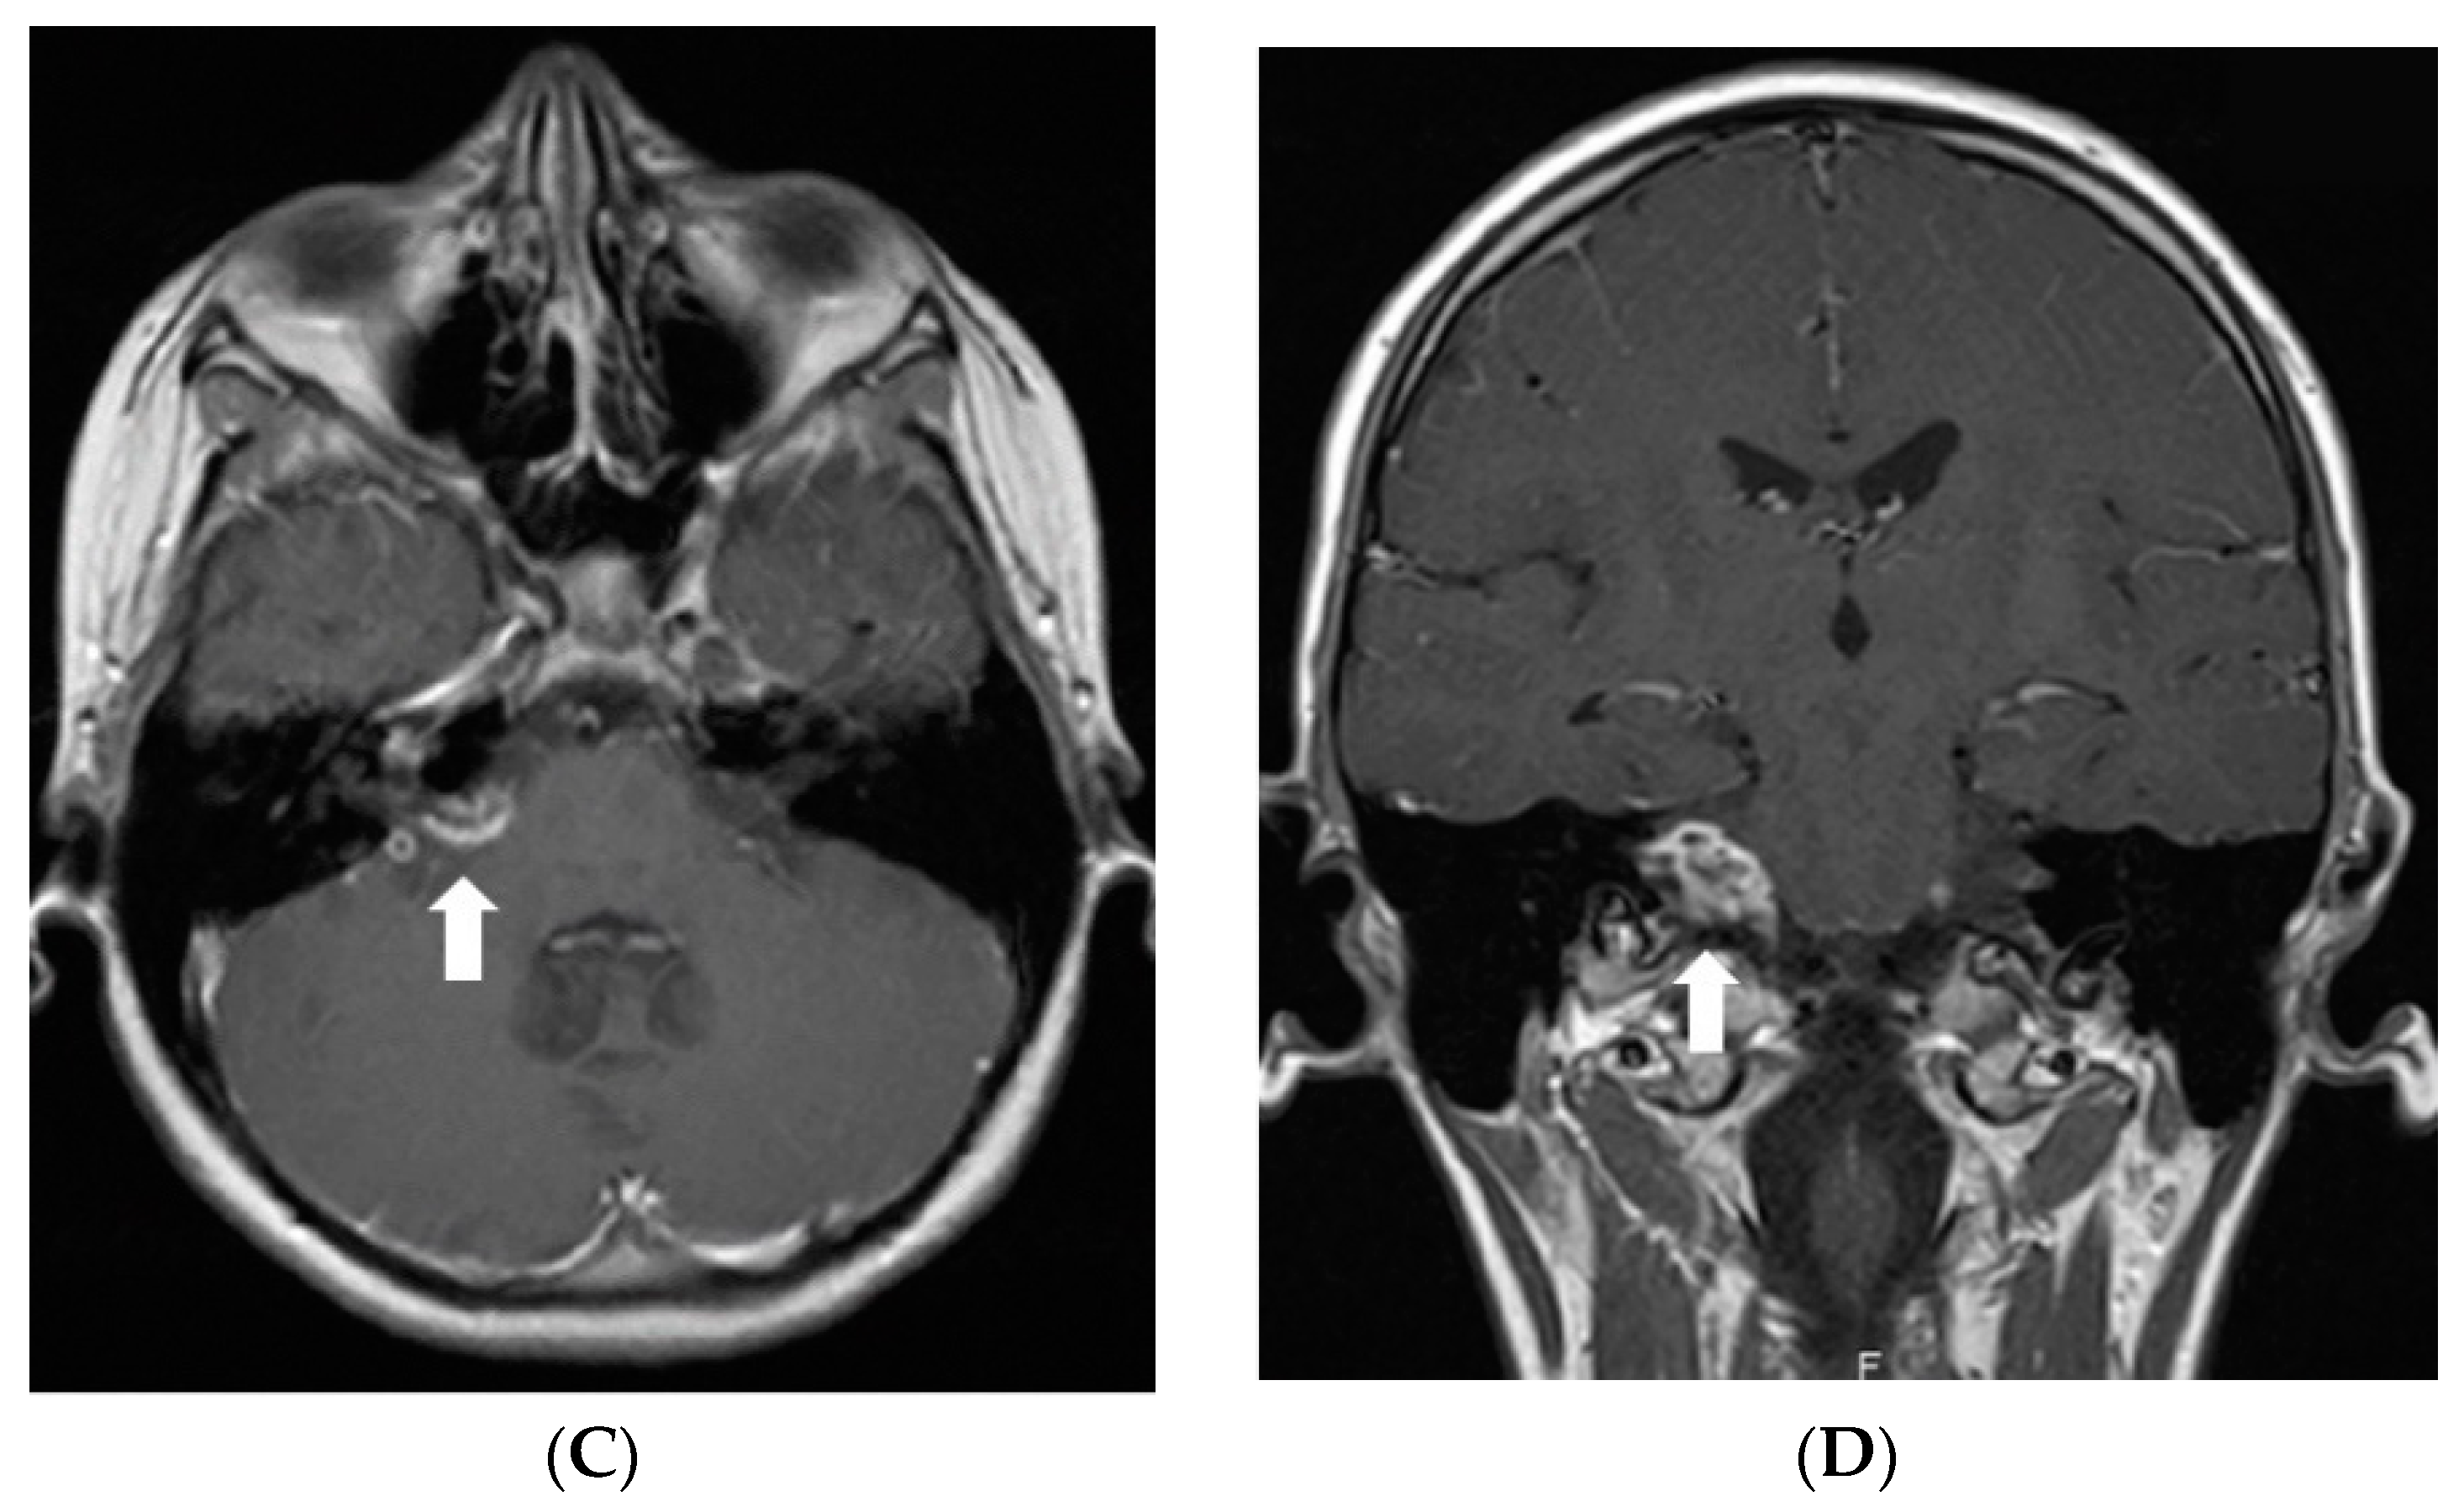

In July 2011, a 16-year-old girl was admitted to Hospital of Lithuanian University of Health Sciences Kauno klinikos due to severe headache, vomiting, and vertigo lasting 2 days. She had a half-year history of similar paroxysms usually beginning with numbness in hands or in one side of face or leg. Neurological examination revealed right-sided peripheral facial paresis, horizontal nystagmus, painful exit points of branches of the right trigeminal nerve, slight deviation of the uvula to the right, right-sided hemiparesis, and cerebellar ataxia. Moreover, papilledema was observed. Brainstem evoked potentials response audiometry showed no clear waves on the right side although hearing was normal. Magnetic resonance imaging (MRI) of the head demonstrated a hyperintense mass on T2W/FLAIR images with heterogenous enhancement in the right cerebellopontine angle cistern and internal auditory canal (Figure 1). All figures in this manuscript are non-published and original.

Figure 1.

Initial MRI of the brain at our clinic (July 2011): (A) Axial T2W/FLAIR and (B) coronal T2W images demonstrate a hyperintense mass in the right cerebellopontine angle cistern and internal auditory canal. (C) Axial and (D) coronal T1W postcontrast images show heterogenous enhancement in the referred area.